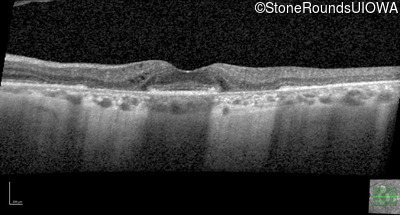

Optical Coherence Tomography - Right - 20/20

Exemplar / OCT Stack

OCT Stack